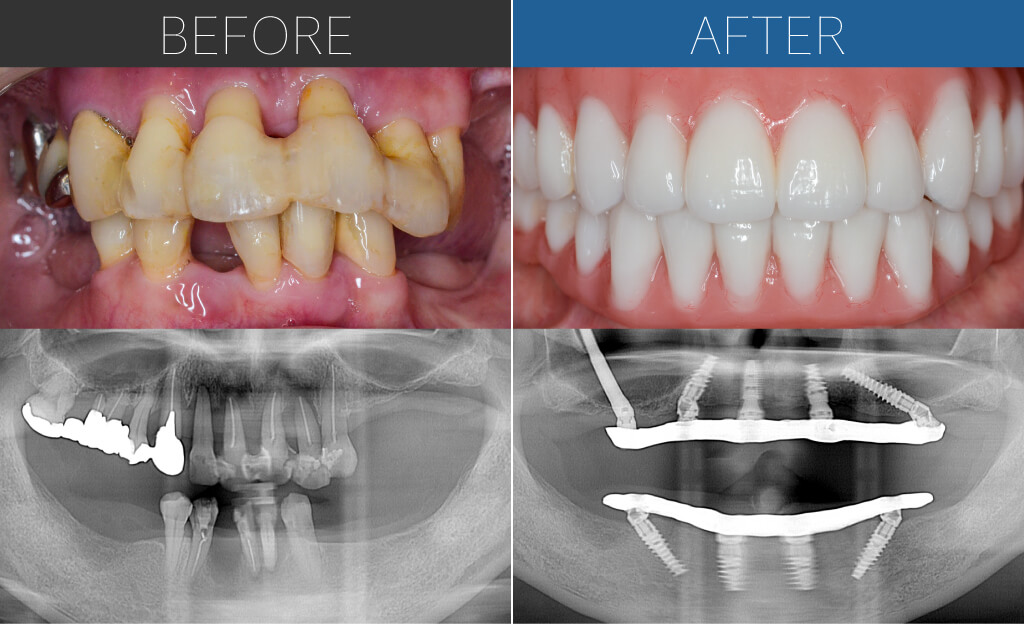

– Upper:All-on-4 + Zygoma + Pterygoid + Wide-Short

– Lower:All-on-4

Age:40s

| 主訴 | 入れ歯を使うと味がしなく食事が美味しくないという理由で、歯がボロボロだけど10年以上入れ歯も使わずに生活されていました。意を決して来院。 |

| 治療内容 | 上顎はザイゴマインプラントにテリゴイド、ワイド・ショートインプラントを含めて8本のインプラントによるオールオン4。下顎は基本的な4本埋入によるオールオン4。上下ともに即時荷重により手術当日に仮歯を固定。 |